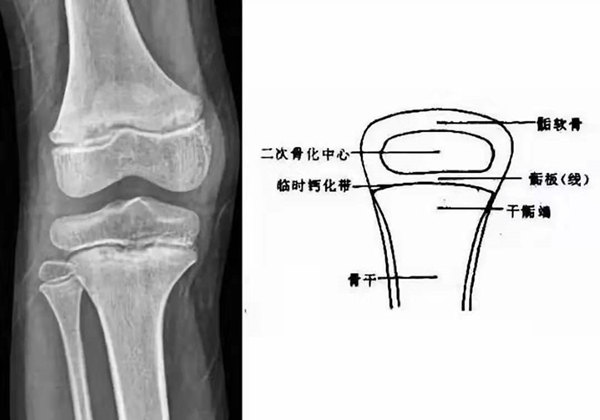

我們都知道,人體的高矮是由骨骼的生長(zhǎng)發(fā)育決定的,特別是下肢長(zhǎng)骨。長(zhǎng)骨呈長(zhǎng)管狀,在長(zhǎng)骨的兩端有一種專管骨骼生長(zhǎng)的骺軟骨,它與干骺端之間有一盤狀軟骨結(jié)構(gòu)稱為骺板(線),在幼兒的X光片上表現(xiàn)為一條較寬的透光帶。 (見(jiàn)下圖)

未成年時(shí)隨著年齡的增加骺軟骨端不斷骨化,骨骼就不斷增長(zhǎng)。當(dāng)骨骺線完全閉合時(shí)骨骼就停止生長(zhǎng),個(gè)子也就不再增長(zhǎng)了。一般骨骺端完全閉合的年齡是18~20歲左右。